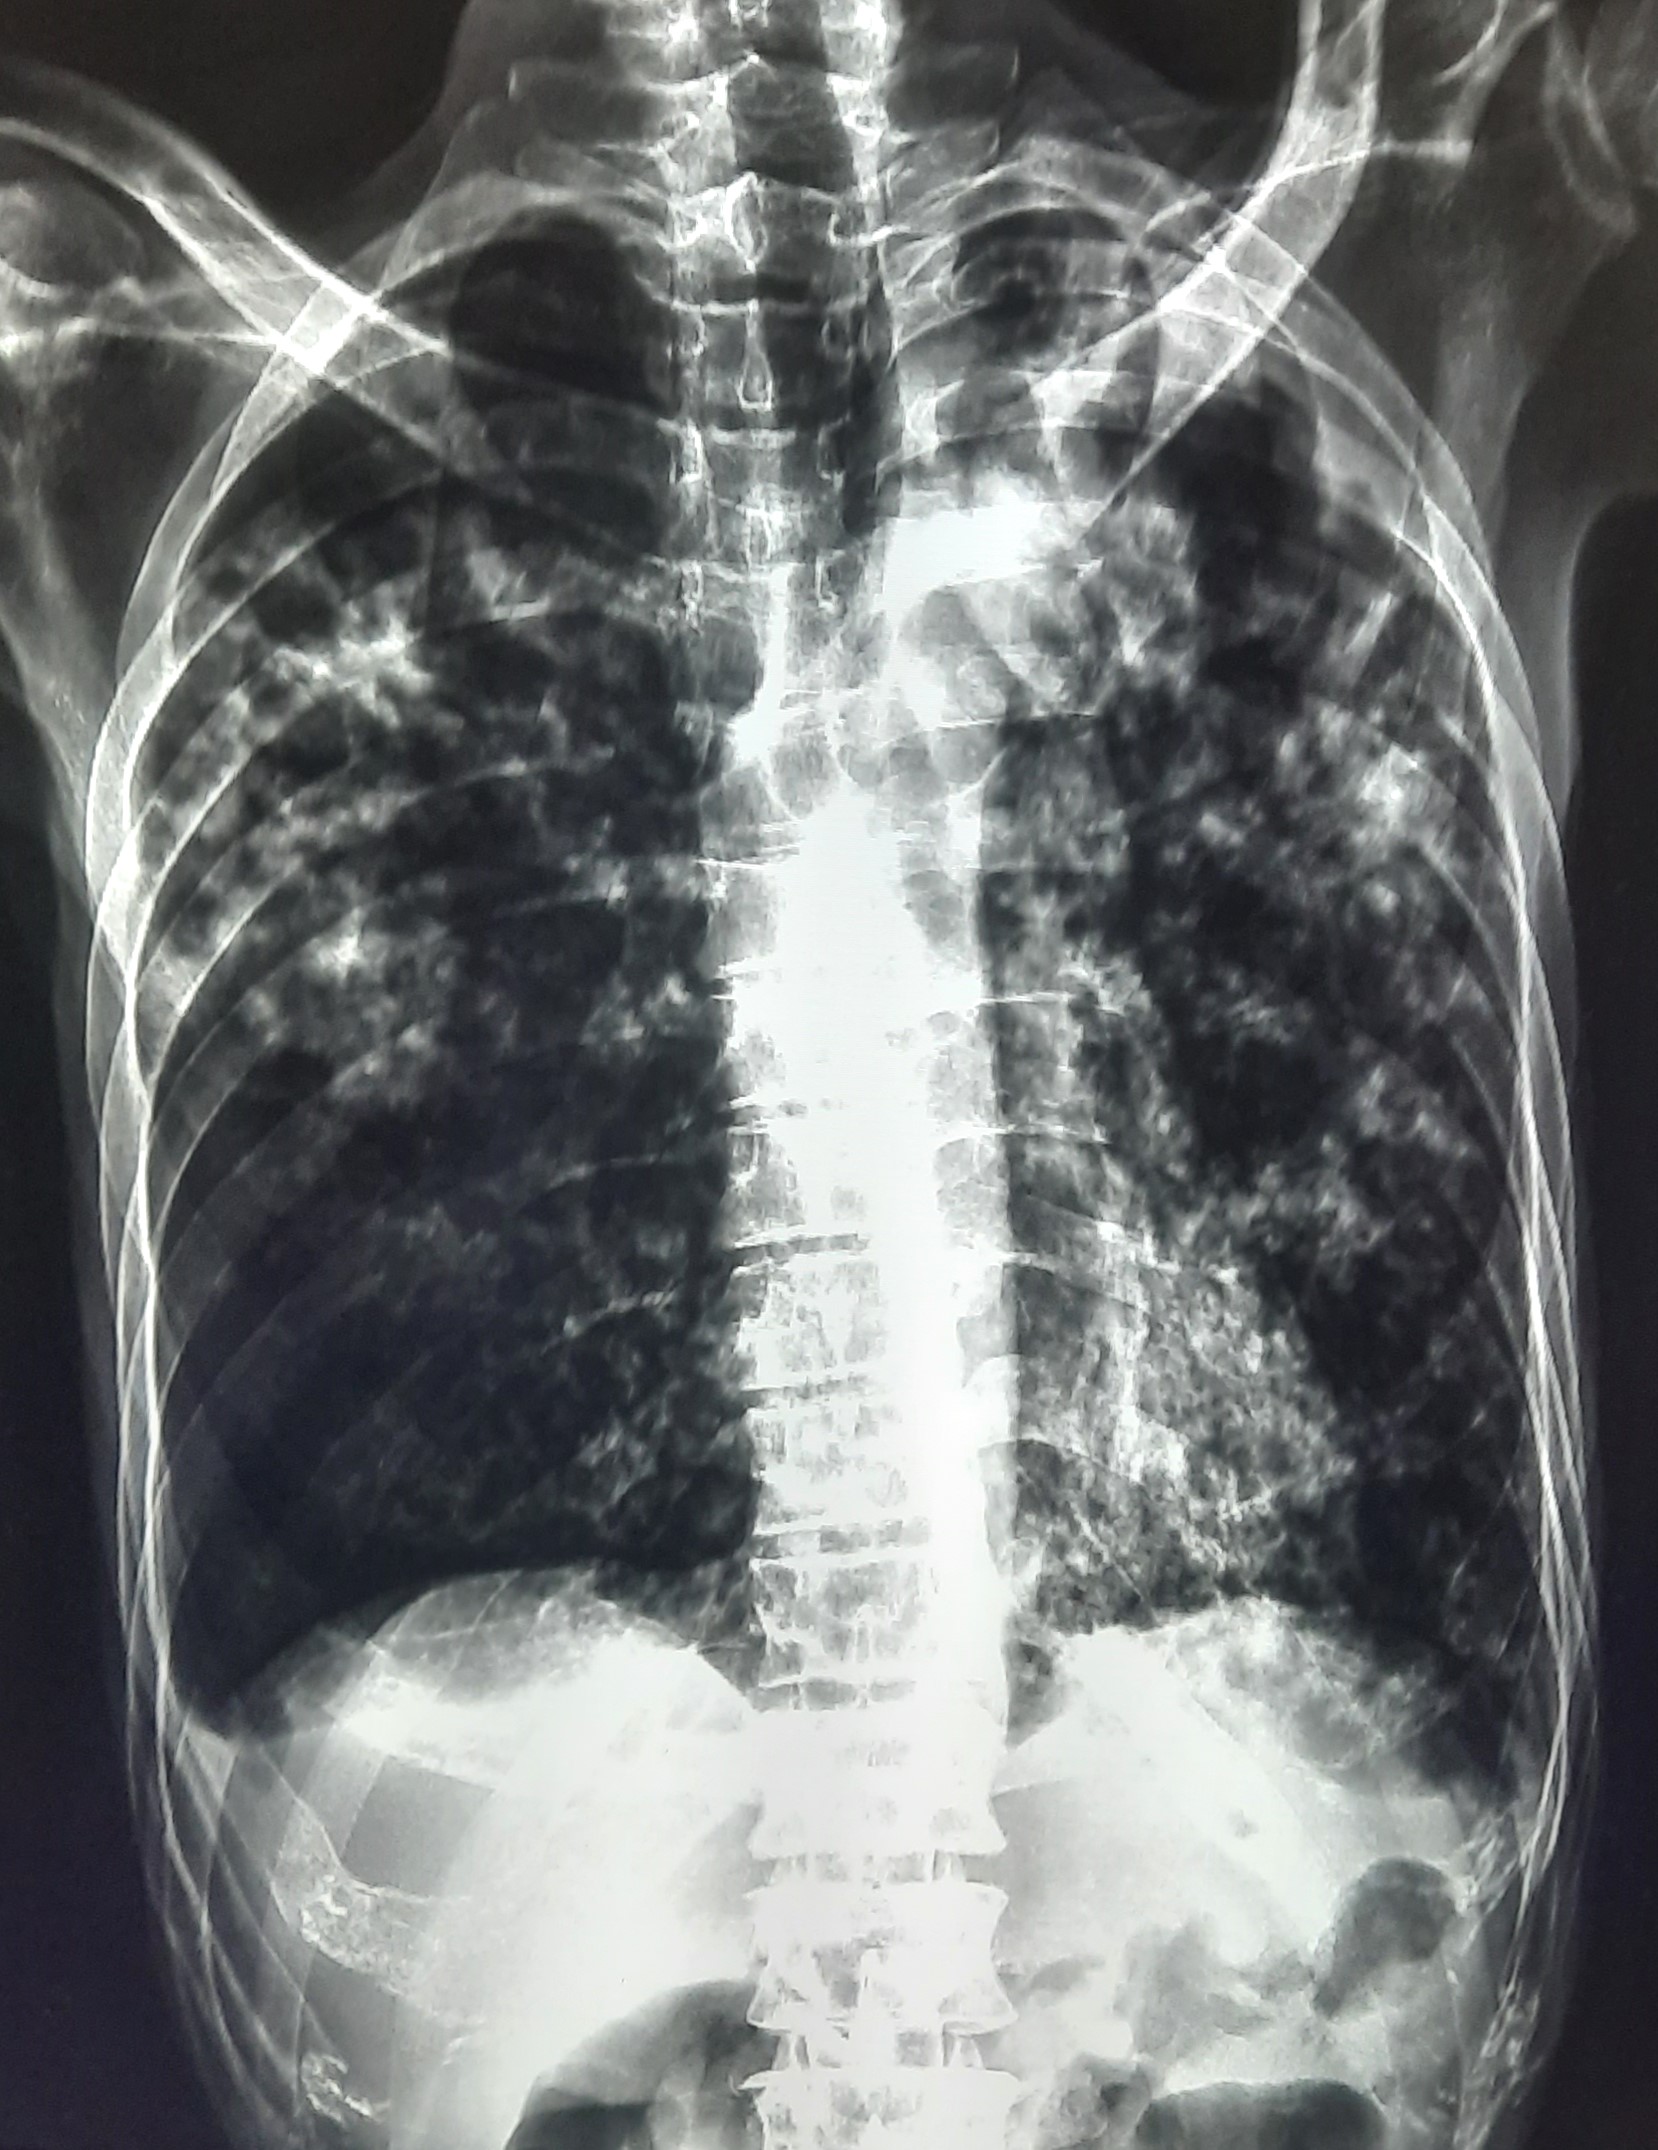

| 54 | IGGMC, Nagpur, Nagpur | P2 | 29-4418 | Pradip Bankar | Consent taken on Paper | 37 Yrs. |

Provisional Diag : Pulmonary Tuberculosis

Final Diag : Pulmonary Tuberculosis (Microbiologically Confirmed PTB) |

TB Case (Confirmed) | Left upper Zone Fibro cavitary lesion Present, Bilateral Lung Infiltration present | Abnormality visible on x-ray |